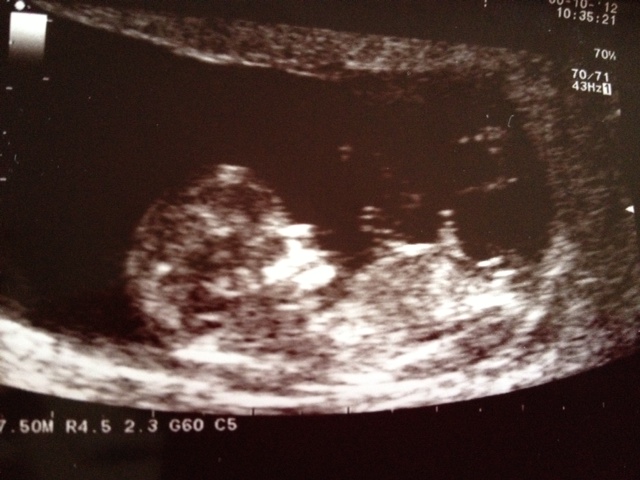

Hi everyone, I'd love to hear what gender you all think my little bundle is. These were taken at 11weeks 5days. Thanks so much in advance for having a look for me :-)

baby looking very younger side can't find the nub clearly

I'm not seeing a clear nub in these images.

Guessing girl from the first pic

Not sure I'm seeing a nub. Skull looks boyish.

50/50. Looks like the nub wasn't well captured. Skull does look boyish, though.